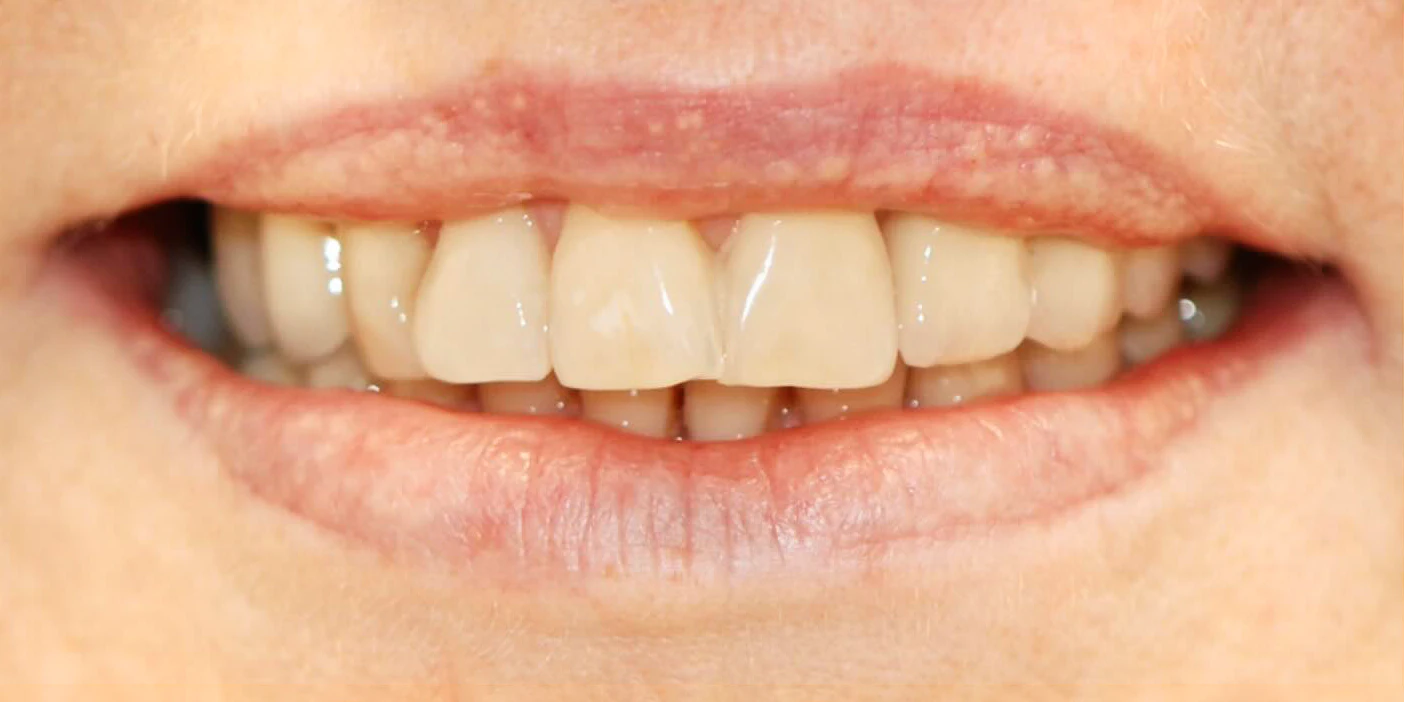

Dzięki cyfrowemu przepływowi pracy, technik mógł zaprojektować i wykonać idealnie pasujące, ceramiczne korony, które zostały przykręcone do implantów. Efekt był zachwycający – zarówno pod względem estetyki, jak i funkcji.

Historia ta pokazuje, że nawet w obliczu zaniku kości, nowoczesna implantologia oferuje skuteczne i bezpieczne rozwiązania. To była długa droga, wymagająca od pacjentki cierpliwości i zaufania, ale jej finał – w postaci pełnego, pięknego i funkcjonalnego uśmiechu – był dla nas obu największą nagrodą.